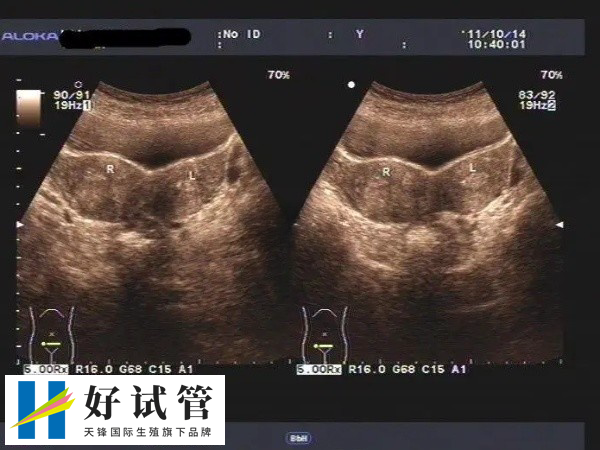

卵泡监测

促排卵期间应定期监测卵泡,指导药物调整,注射或不注射HCG监测卵泡发育情况,直至卵泡接近成熟大小(18-20cm)。同时,我们还可以通过基础体温、宫颈粘液评分、血尿激素等来监测卵泡的发育情况。大概在400-1000元之间。